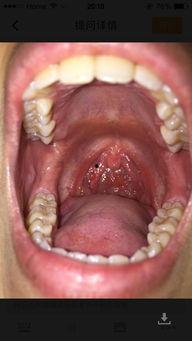

那么,喉咙发炎的时候,吃凉瓜有用吗?这个问题,其实并没有一个绝对的答案。因为喉咙发炎的原因有很多,比如病毒感染、细菌感染、过敏等,而凉瓜的作用主要是清热解毒。

如果是病毒感染引起的喉咙发炎,吃凉瓜可能会有一定的帮助。因为苦瓜中的生物碱成分具有一定的抗病毒作用,可以增强免疫力,帮助身体抵抗病毒。

如果是细菌感染引起的喉咙发炎,吃凉瓜可能就没有太大的作用了。因为细菌感染需要抗生素来治疗,而凉瓜并不能替代抗生素的作用。

如果是过敏引起的喉咙发炎,吃凉瓜可能也没有太大的帮助。因为过敏需要找到过敏源并避免接触,同时可能需要抗过敏药物来缓解症状。